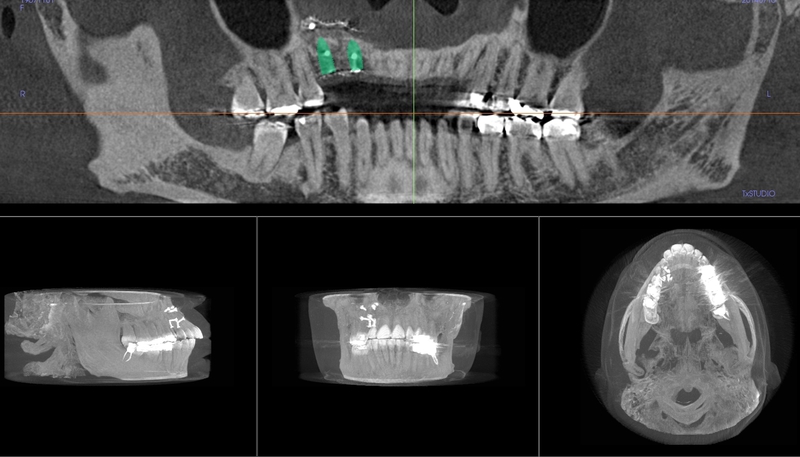

CT Scanner for Optimal Treatment Planning

New iCAT CT scanner offers precise imaging with radiation comparable to traditional x-ray units.  Using this 3D imaging technology the doctor can accurately plan surgery, avoid complications, and create custom implant treament plans.

The CT scanner's imaging allows us to create custom made surgical guides specific to each patient.  These surgical guides allow the precise placement of dental implants for optimal functional and esthetic results.

CT Guided Custom Implant Placment

A Case with a Fractured Central Incisor